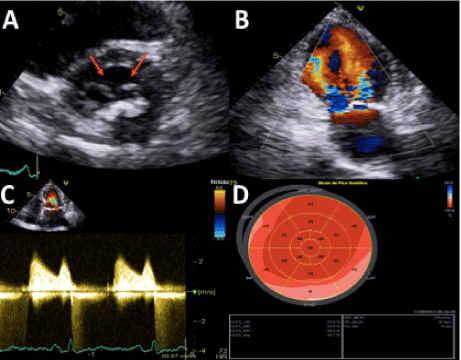

In this case report, we present a 76-year-old female patient, without cardiovascular comorbidities, who was diagnosed with invasive ductal carcinoma of the left breast (clinical stage IIIC) in 2016. Right after the initial diagnosis, she underwent total mastectomy and started adjuvant chemotherapy with Adriamycin and cyclophosphamide every 21 days for 2 months. After a month of interval, the patient gave sequence with paclitaxel weekly for about 3 months. And a month after the end of chemotherapy, the radiotherapy treatment started for another month (5000cGy). Four months before the beginning of the chemotherapy treatment, an echocardiogram was performed, which showed only a slight thickening of the mitral valve, but there were no significant morpho-functional changes, being described as open and preserved mobility and without DOMV. Two months after the end of the radiotherapy treatment and 10 months after the start of the chemotherapy treatment, a new echocardiogram was performed, and demonstrated an important alteration of the mitral valve anatomy, which became fibrocalcified and evolved by mild to moderate stenosis. However, the description of absence of DOMV in the valve was maintained. Due to this rapid and significant pre and post treatment evolution, a new echocardiogram was requested for a more complete evaluation of the patient’s condition. In this new examination, the presence of a mitral valve with thickened cusps combined with significant calcification, and the presence of a double orifice valve opening associated to severe mitral stenosis (mean diastolic mitral flow gradient = 14 mmHg and VA = 0.9 cm2 by planimetry) was evidenced (Figure 1).

Figure 1. Conventional transthoracic echocardiography views. A: The parasternal short-axis view revealed double-orifice mitral valve (red arrows); B: Color-Doppler echocardiography in the apical two-chamber view demonstrated two separate inflow jets; C: Pulsed-wave Doppler spectrum of the velocity time integral of the mitral valve; D: Global longitudinal strain of the LV. LV indicates left ventricle.